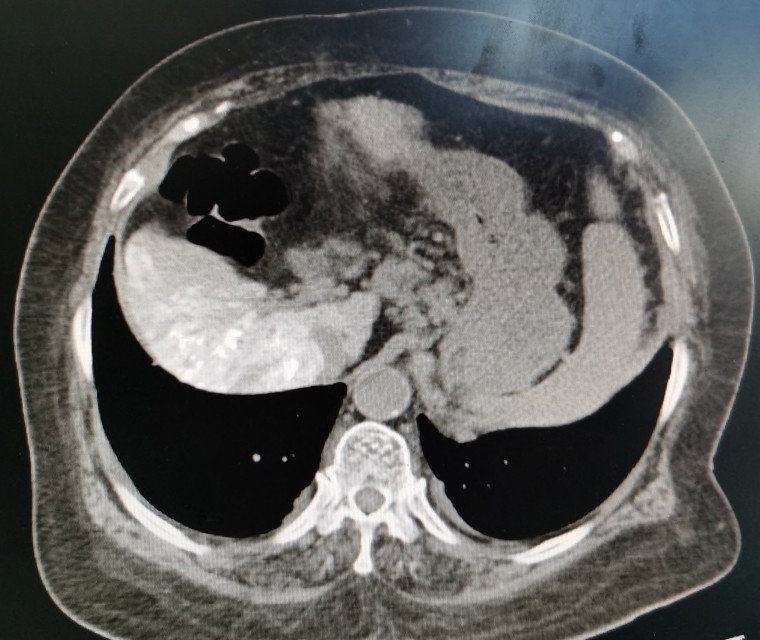

栓塞后的影像图

第一次肝动脉导管栓塞化疗术后,黄婶出现了严重的高热、腹胀和肝肾功能不全,经各种治疗后大概1周左右病情基本稳定。这次保驾护航成功以后,黄婶每次治疗都来找我,哪儿都不去,弄得我压力山大。

栓塞后复查的CT

栓塞后CT

肿瘤栓塞良好